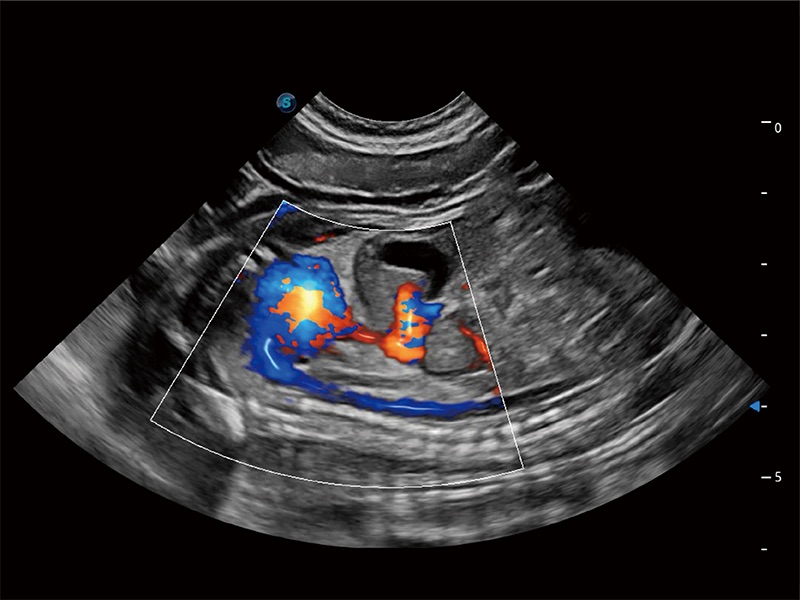

极大提升超低速微细血流的检出能力,同时更精准地滤除软组织和超声信号,为兽用医生提供以往无法通过常规血流获得的疾病诊断信息。

在传统二维血流成像的基础上,呈现血流的立体感,具有动感的生命力之美。即便是微小的血管也能轻松应对,提高了血流的视觉敏感性。